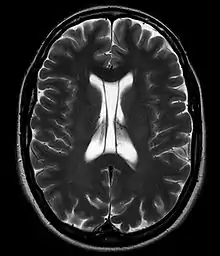

Размер полости крайне вариабелен, у некоторых полость полностью закрыта, в то время как у других отмечается практически полное её незаращение (до 46 мм в корональной плоскости).[3]

В большинстве случаев полость не сообщается с полостью желудочковой системы мозга, что делает неправомочным её описание как «5-го желудочка» головного мозга, тем не менее, иногда её называют пятым желудочком.

Собственно полость прозрачной перегородки расположена на уровне основания передних рогов боковых желудочков мозга, а её распространение в заднем направлении в область тел боковых желудочков выделяют под названием полость Верге (лат. cavum vergae). Во время эмбрионального развития происходит закрытие полостей в задне-переднем направлении, из-за чего персистирование полости Верге при закрытой полости прозрачной перегородки встречается значительно реже.

В то же время отмечается некоторое увеличение частоты встречаемости полости прозрачной перегородки у пациентов с шизофренией[6], посттравматическим стрессовым расстройством[7], черепно-мозговой травмой[8], а также диссоциальным расстройством личности[3]. Наличие расширенной полости — один из отличительных признаков пациентов с травматической энцефалопатией боксеров (dementia pugilistica).[9]